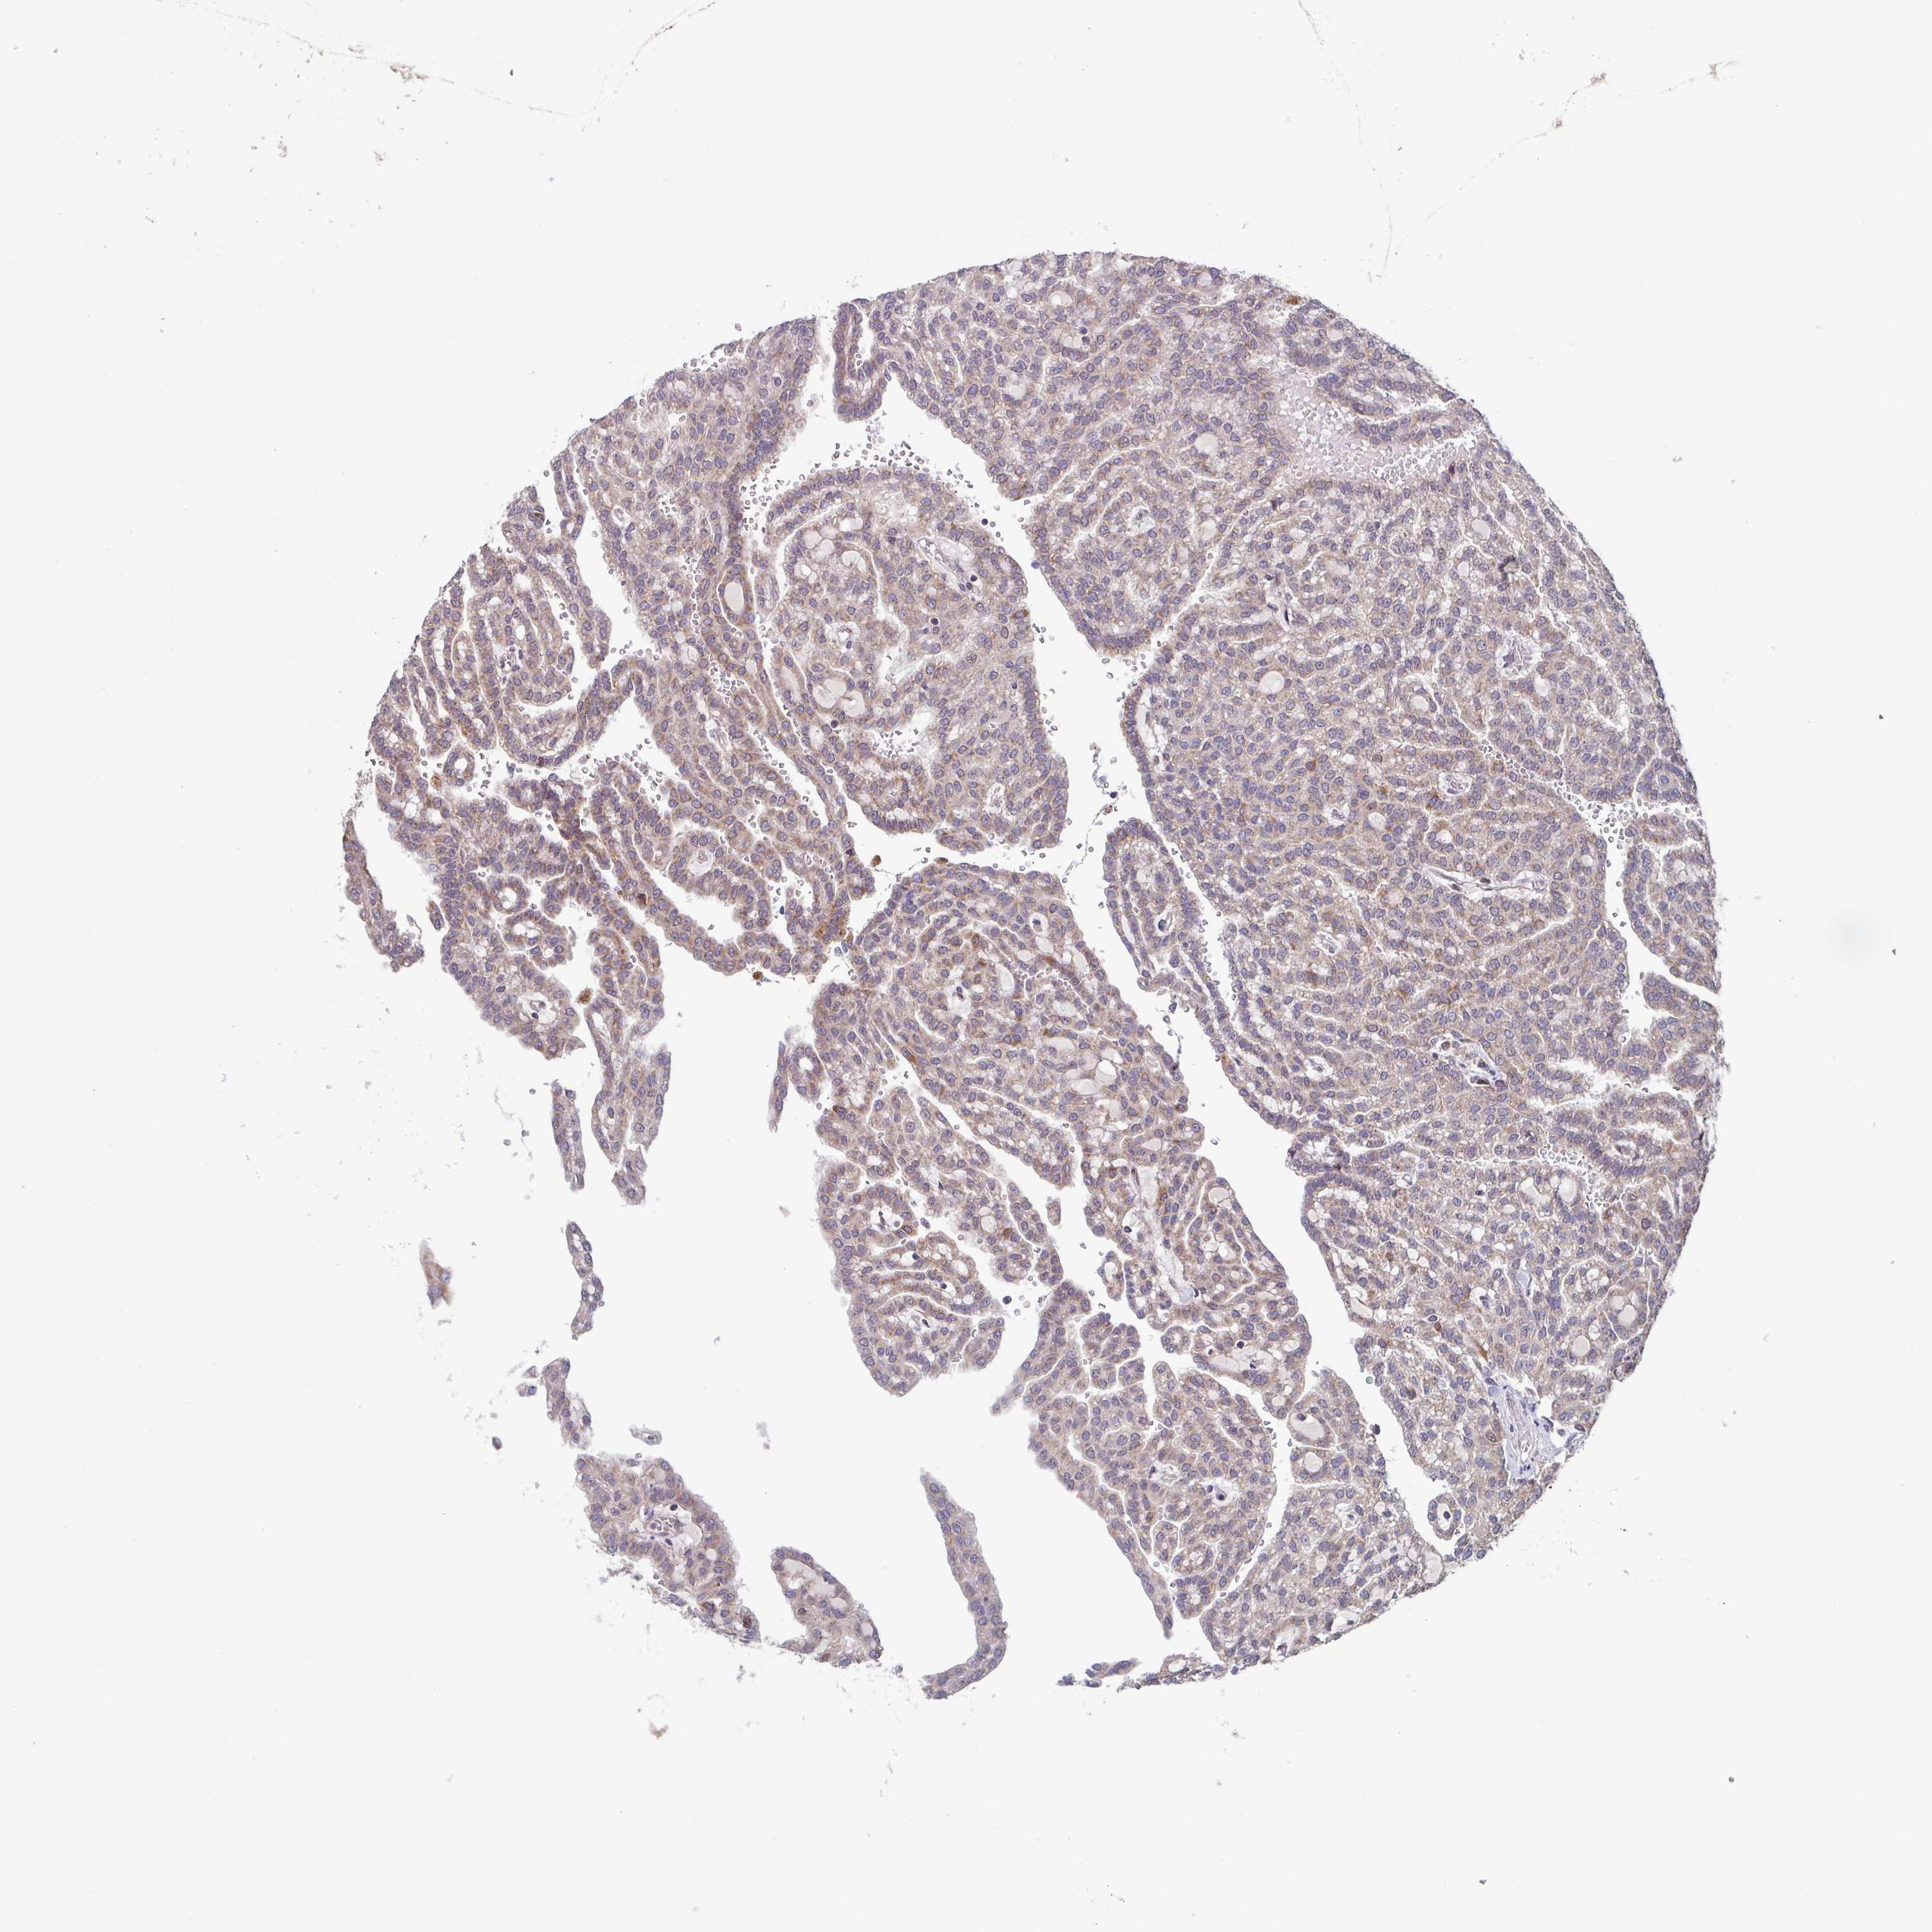

KIDNEY RENAL CLEAR CELL CARCINOMA (VALIDATION) - Interactive survival scatter ploti

The Survival Scatter plot shows the clinical status (i.e. dead or alive) for all individuals in the patient cohort, based on the same data that underlies the corresponding Kaplan-Meier plots. Patients that are alive at last time for follow-up are shown in blue and patients who have died during the study are shown in red.

The x-axis shows the expression levels (FPKM) of the investigated gene in the tumor tissue at the time of diagnosis. The y-axis shows the follow-up time after diagnosis (years). Both axes are complimented with kernel density curves demonstrating the data density over the axes. The top density plot shows the expression levels (FPKM) distribution among dead (red) and alive patients (blue). The right density plot shows the data density of the survived years of dead patients with high and low expression levels respectively, stratified using the cutoff indicated by the vertical dashed line through the Survival Scatter plot. This cutoff is automatically defined based on the FPKM cutoff that minimizes the p-score. The cutoff can be changed by dragging the vertical line or by entering a cutoff value in the square labeled "Current cut-off".

Under the Survival Scatter plot the p-score landscape (black curve; left axis) is shown together with dead median separation (red curve; right axis). Dead median separation is the difference in median mRNA expression between patients who have died with high and low expression, respectively. It is calculated as follows: median FPKM expression of dead patients with high expression - median FPKM expression of dead patients with low expression. This is intended to aid the user in visually exploring custom cutoffs and the associated p-scores and dead median separation.

Individual patient data is displayed and can be filtered by clicking on one or more of the category buttons on the top of the page. Categories describing expression level and patient information include: high, low, alive, dead, female, male and tumor stages. The scale of the x-axis can be toggled between linear and log-scale by clicking on the "x log" button. Mouse-over function shows TCGA ID, patient information and mRNA expression (FPKM) for each patient.

& Survival analysisi

Kaplan-Meier plots summarize results from analysis of correlation between mRNA expression level and patient survival. Patients were divided based on level of expression into one of the two groups "low" (under cut off) or "high" (over cut off). X-axis shows time for survival (years) and y-axis shows the probability of survival, where 1.0 corresponds to 100 percent.

TTC19 is not prognostic in Kidney Renal Clear Cell Carcinoma (validation)

Best expression cut offi

Based on the FPKM value of each gene, patients were classified into two groups and association between prognosis (survival) and gene expression (FPKM) was examined. The best expression cut-off refers the FPKM value that yields maximal difference with regard to survival between the two groups at the lowest log-rank P-value. Best expression cut-off was selected based on survival analysis .

When clicking on this number, the vertical dashed line indicating cut-off, the interactive survival plot, and the Kaplan-Meier curve will be adjusted to show results based on the best expression cut-off.

: 7.41

P scorei

Log-rank P value for Kaplan-Meier plot showing results from analysis of correlation between mRNA expression level and patient survival.

N/A

TCGA RNA samplesi

RNA-seq data is reported as average FPKM (number Fragments Per Kilobase of exon per Million reads), generated by the The Cancer Genome Atlas (TCGA) .

Normal distribution across the dataset is visualized with box plots, shown as median and 25th and 75th percentiles. Points are displayed as outliers if they are above or below 1.5 times the interquartile range. FPKM values of the individual samples are presented next to the box plot.

Average pTPM 7.5

Number of samples 100